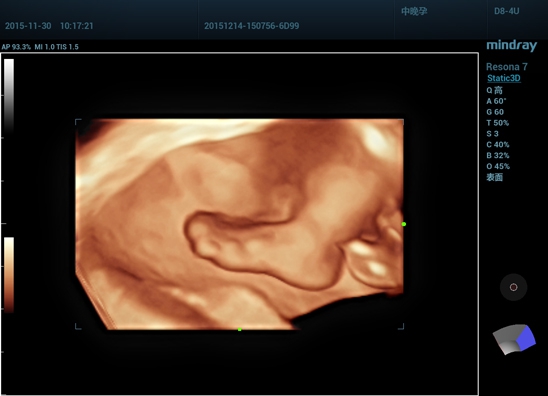

• получение трехмерного изображения с помощью объемных датчиков (Static 3D);

• получение трехмерного изображения в реальном режиме времени (4D);